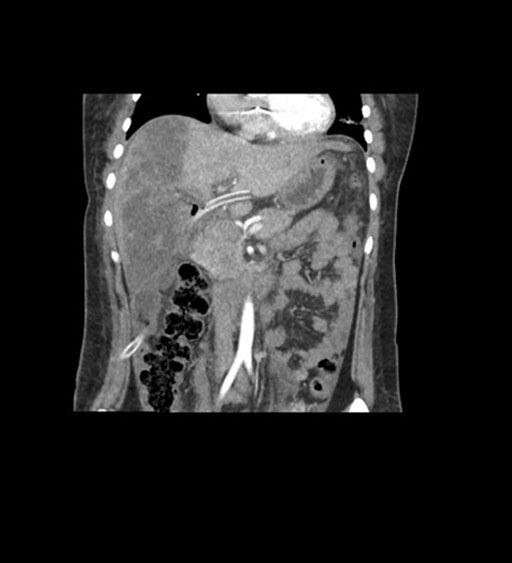

Imaging Analysis

Look through the patient's CT scan to identify any areas of concern for the necessary procedure.

Coronal Arterial

Coronal Venous

Based on initial findings, which issue(s) would you be most concerned about?